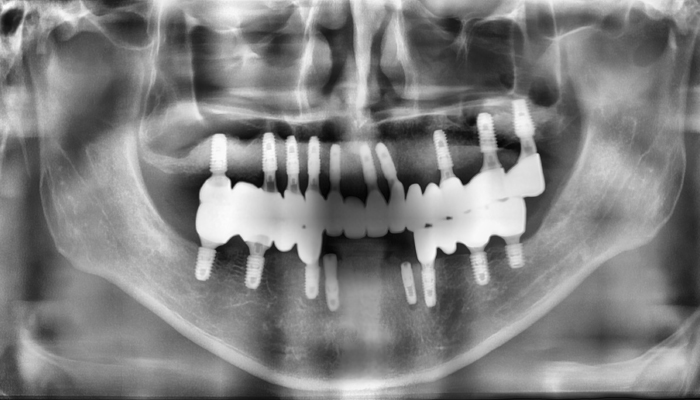

틀니 임플란트 전후 사례

• 식립전

식립후